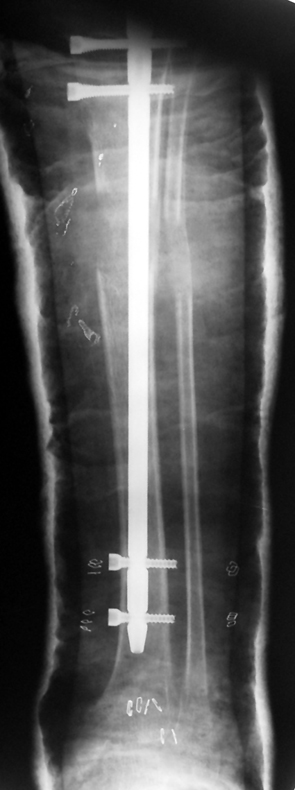

3. POSTTRAUMATIC LOWER LIMB SHORTNESS (MALUNION)

This type of shortness occurs after a fracture heals in a shortened position. Most cases are seen in adults and can be treated with one lengthening operation. Additional deformities can be corrected simultaneously. Most of these cases can be treated with lengthening over nail or just corrections and intramedullary nailing.